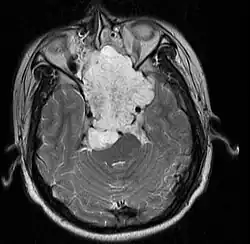

| MRI of extensive clival chordoma in 17-year-old male patient, axial view. Tumor in the nasopharynx extending from nasal cavity to brainstem posteriorly is clearly visible. | |

Chordomas can arise from bone in the skull base and anywhere along the spine. The two most common locations are cranially at the clivus and in the sacrum at the bottom of the spine.[2] Very rarely, chordomas present outside of the skull base or spine; these are called extra axial chordomas.[3]

In most cases, complete surgical resection followed by radiation therapy offers the best chance of long-term control.[17] Incomplete resection of the primary tumor makes controlling the disease more difficult and increases the odds of recurrence. The decision whether complete or incomplete surgery should be performed primarily depends on the anatomical location of the tumor and its proximity to vital parts of the central nervous system.[18]

Chordomas are relatively radioresistant, requiring high doses of radiation to be controlled. The proximity of chordomas to vital neurological structures such as the brain stem and nerves limits the dose of radiation that can safely be delivered. Therefore, highly focused radiation such as proton therapy and carbon ion therapy are more effective than conventional x-ray radiation.[19]